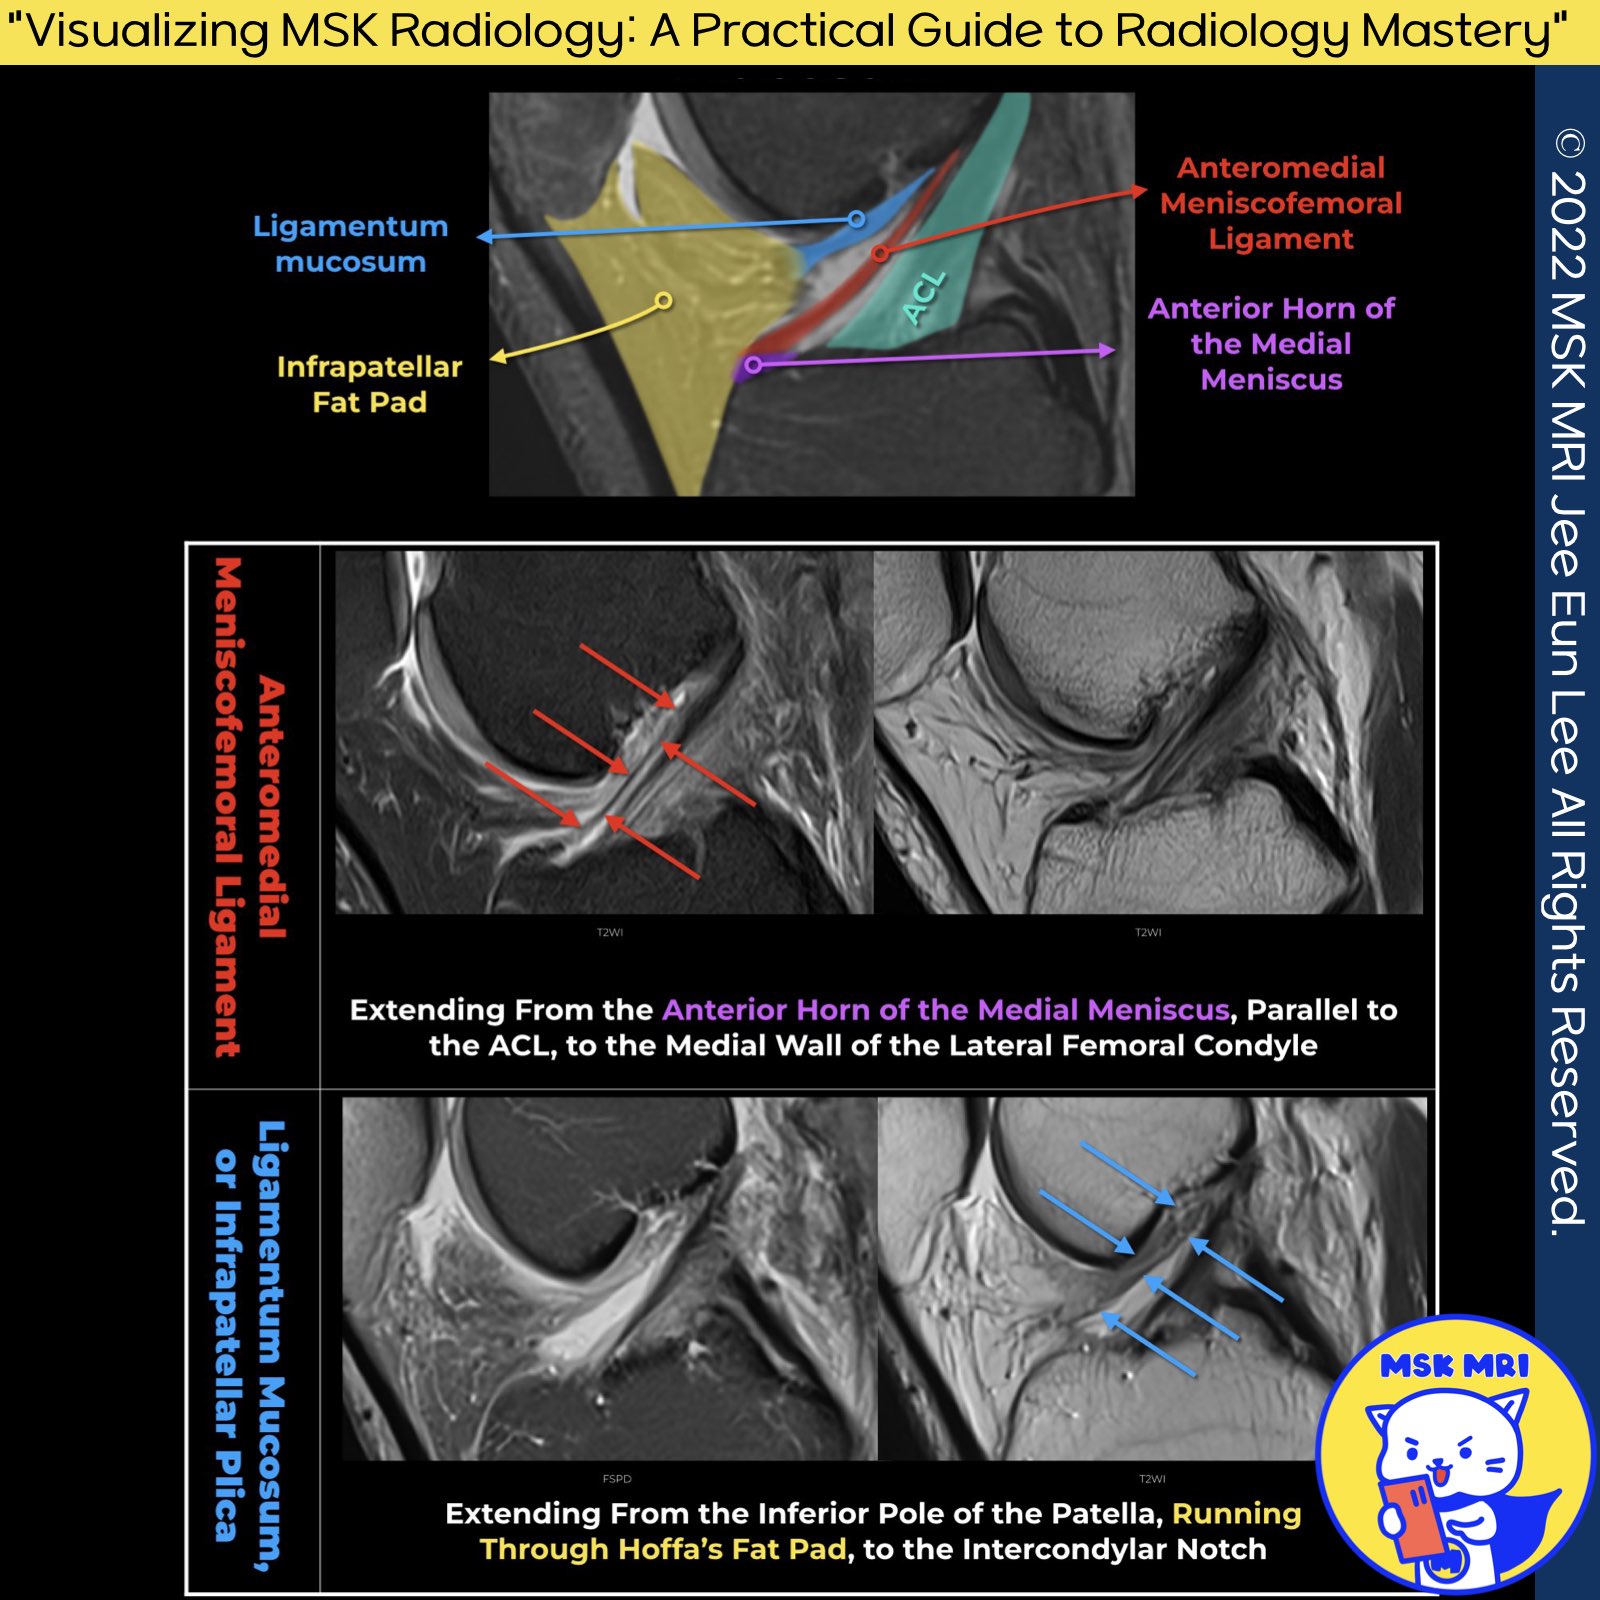

Comparison of Anteromedial Meniscofemoral Ligament and Ligamentum Mucosum

1️⃣ Anteromedial Meniscofemoral Ligament (AMML):

- Definition: An uncommon accessory ligament that extends from the anterior horn of the medial meniscus, running parallel to the Anterior Cruciate Ligament (ACL), to insert into the medial wall of the lateral femoral condyle adjacent to the ACL insertion.

- Location and Course: The AMML is noted for its straight course, distinguishing it from other ligamentous structures within the knee, with a specific anterior insertion into the medial meniscus.

2️⃣ Ligamentum Mucosum (Infrapatellar Plica):

- Definition: A centrally located synovial fold within the knee, extending from the inferior pole of the patella through Hoffa’s fat pad and to the intercondylar notch, paralleling the ACL.

- Plicae Overview: The knee contains three main plicae - suprapatellar, infrapatellar (Ligamentum Mucosum), and medial patellar, which are synovial folds that play roles in knee structure and function.

📌 Key Differences:

- Course and Insertion: The primary difference between AMML and Ligamentum Mucosum lies in their course and points of insertion. AMML is distinguished by its straight course and anterior insertion into the medial meniscus, whereas the Ligamentum Mucosum (infrapatellar plica) inserts into Hoffa’s fat pad, with a central location that runs through the knee.